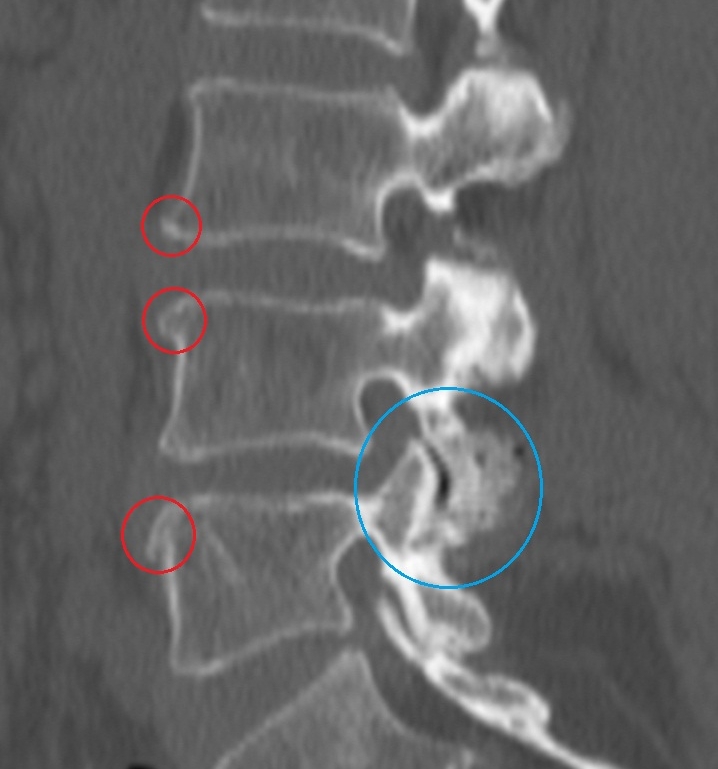

- Рентгенография. Снимки выполняются в прямой и боковой проекции. Для получения полной картины патологии и ее возможного развития делаются снимки всего позвоночного столба. Эти изображения помогают оценить границы и степень патологии, а также объем изменений в местах соединения ребер и позвоночника.

- Магнитно-резонансная томография. Этот метод предоставляет детальную информацию о размерах остеофитов, степени срастания позвонков и величине деформации хрящевых дисков. МРТ также позволяет оценить состояние суставов, сосудов и нервных волокон.